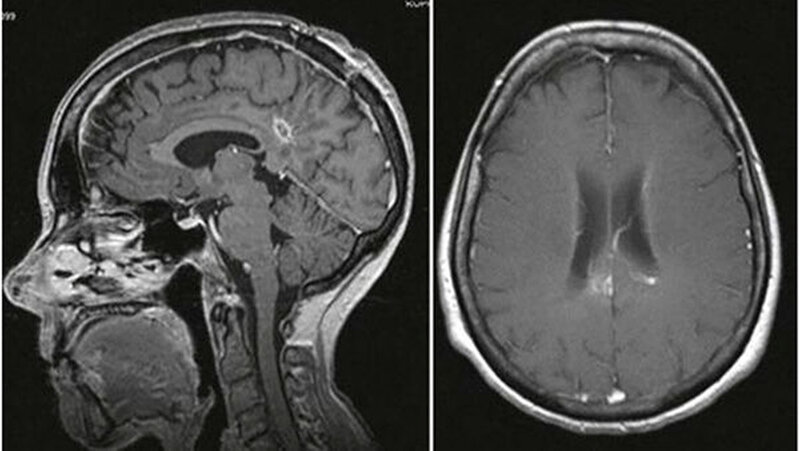

Nach weiteren zwei Wochen ergab ein CT das Wiedervorhandensein einer raumfordernden Läsion. Die Patientin zeigte zudem Fieber und ansteigende inflammatorische Serumparameter. Daraufhin wurde eine Biopsie und Entleerung der Flüssigkeitsansammlung durchgeführt. Die intraoperative Analyse zeigte aktivierte Makrophagen und Leukozyten entsprechend einem Gehirnabszess. Die vorhergehende Antibiose wurde prolongiert und um Ampicillin erweitert. Zudem wurde eine geringe Dosis an Dexamethason verabreicht, um einer weiteren Ödembildung vorzubeugen. Nach einer Woche befand sich die Patientin in einem stabilen Zustand ohne neurologische Störungen. Ein MRT bestätigte eine Läsionsreduktion (Abb. 2).